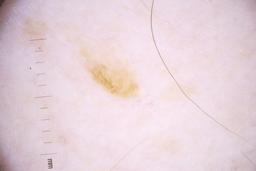

- Name: Challenge 2020: Training

- Number of images: 33,126

- Number of specified lesions: 32,701

- Number of specified patients: 2,056